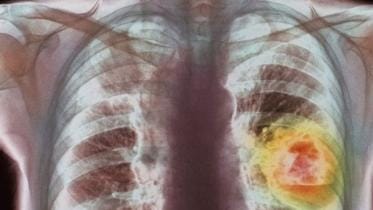

lung cancer

Air pollution fuels lung cancer among non-smokers: study

Lung cancer is the commonest form of the disease, with 2.5 million people diagnosed in 2022